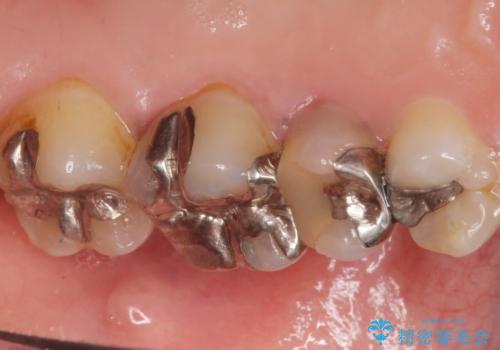

歯ぐきを押すと痛い 神経が死んでいる歯の治療 40代女性

- 歯の根のあたりの歯ぐきを押すと痛むことを主訴に来院された患者様です。

精査したところ、左上の小臼歯(左上5)の神経が死んでいました。

根管治療後、セラミッククラウンによる補綴を行いました。